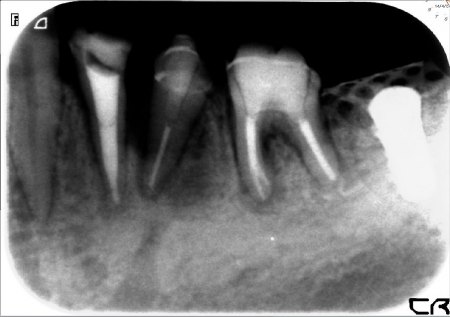

破折片除去 根管治療

かなもり歯科クリニックでは

拡大鏡.マイクロスコープを用い

異物除去をおこない精度の高い根管治療を行っております

すべての異物が除去できるわけではありませんが

患者様の希望があるかぎりしぶとく!!